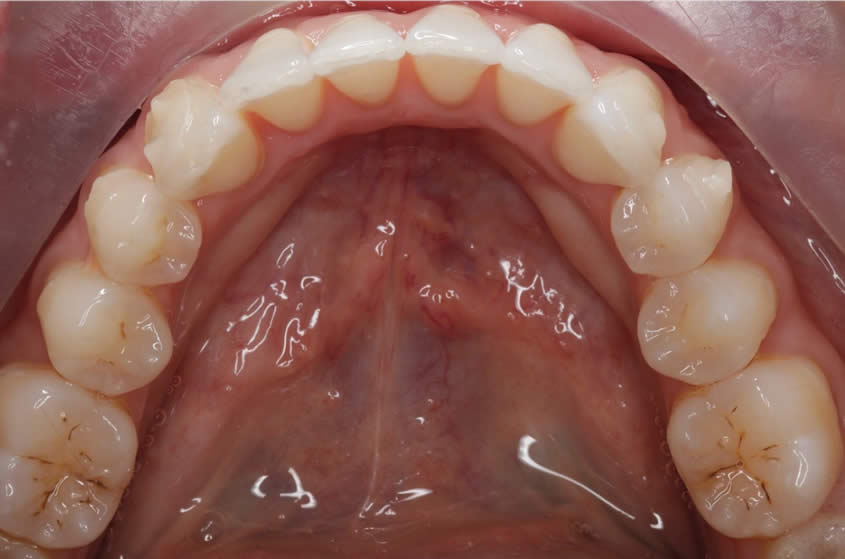

Patient Teeth Straightening Case

Teeth Straightening - Case 1